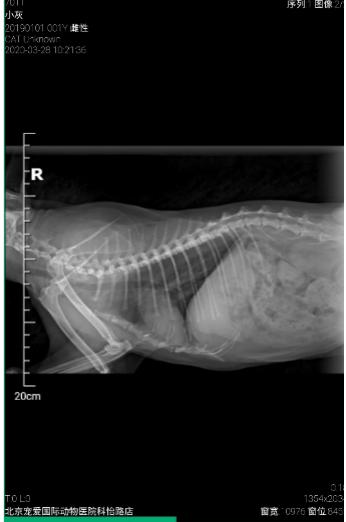

超声和DR检查

未见腹腔、胸腔内转移